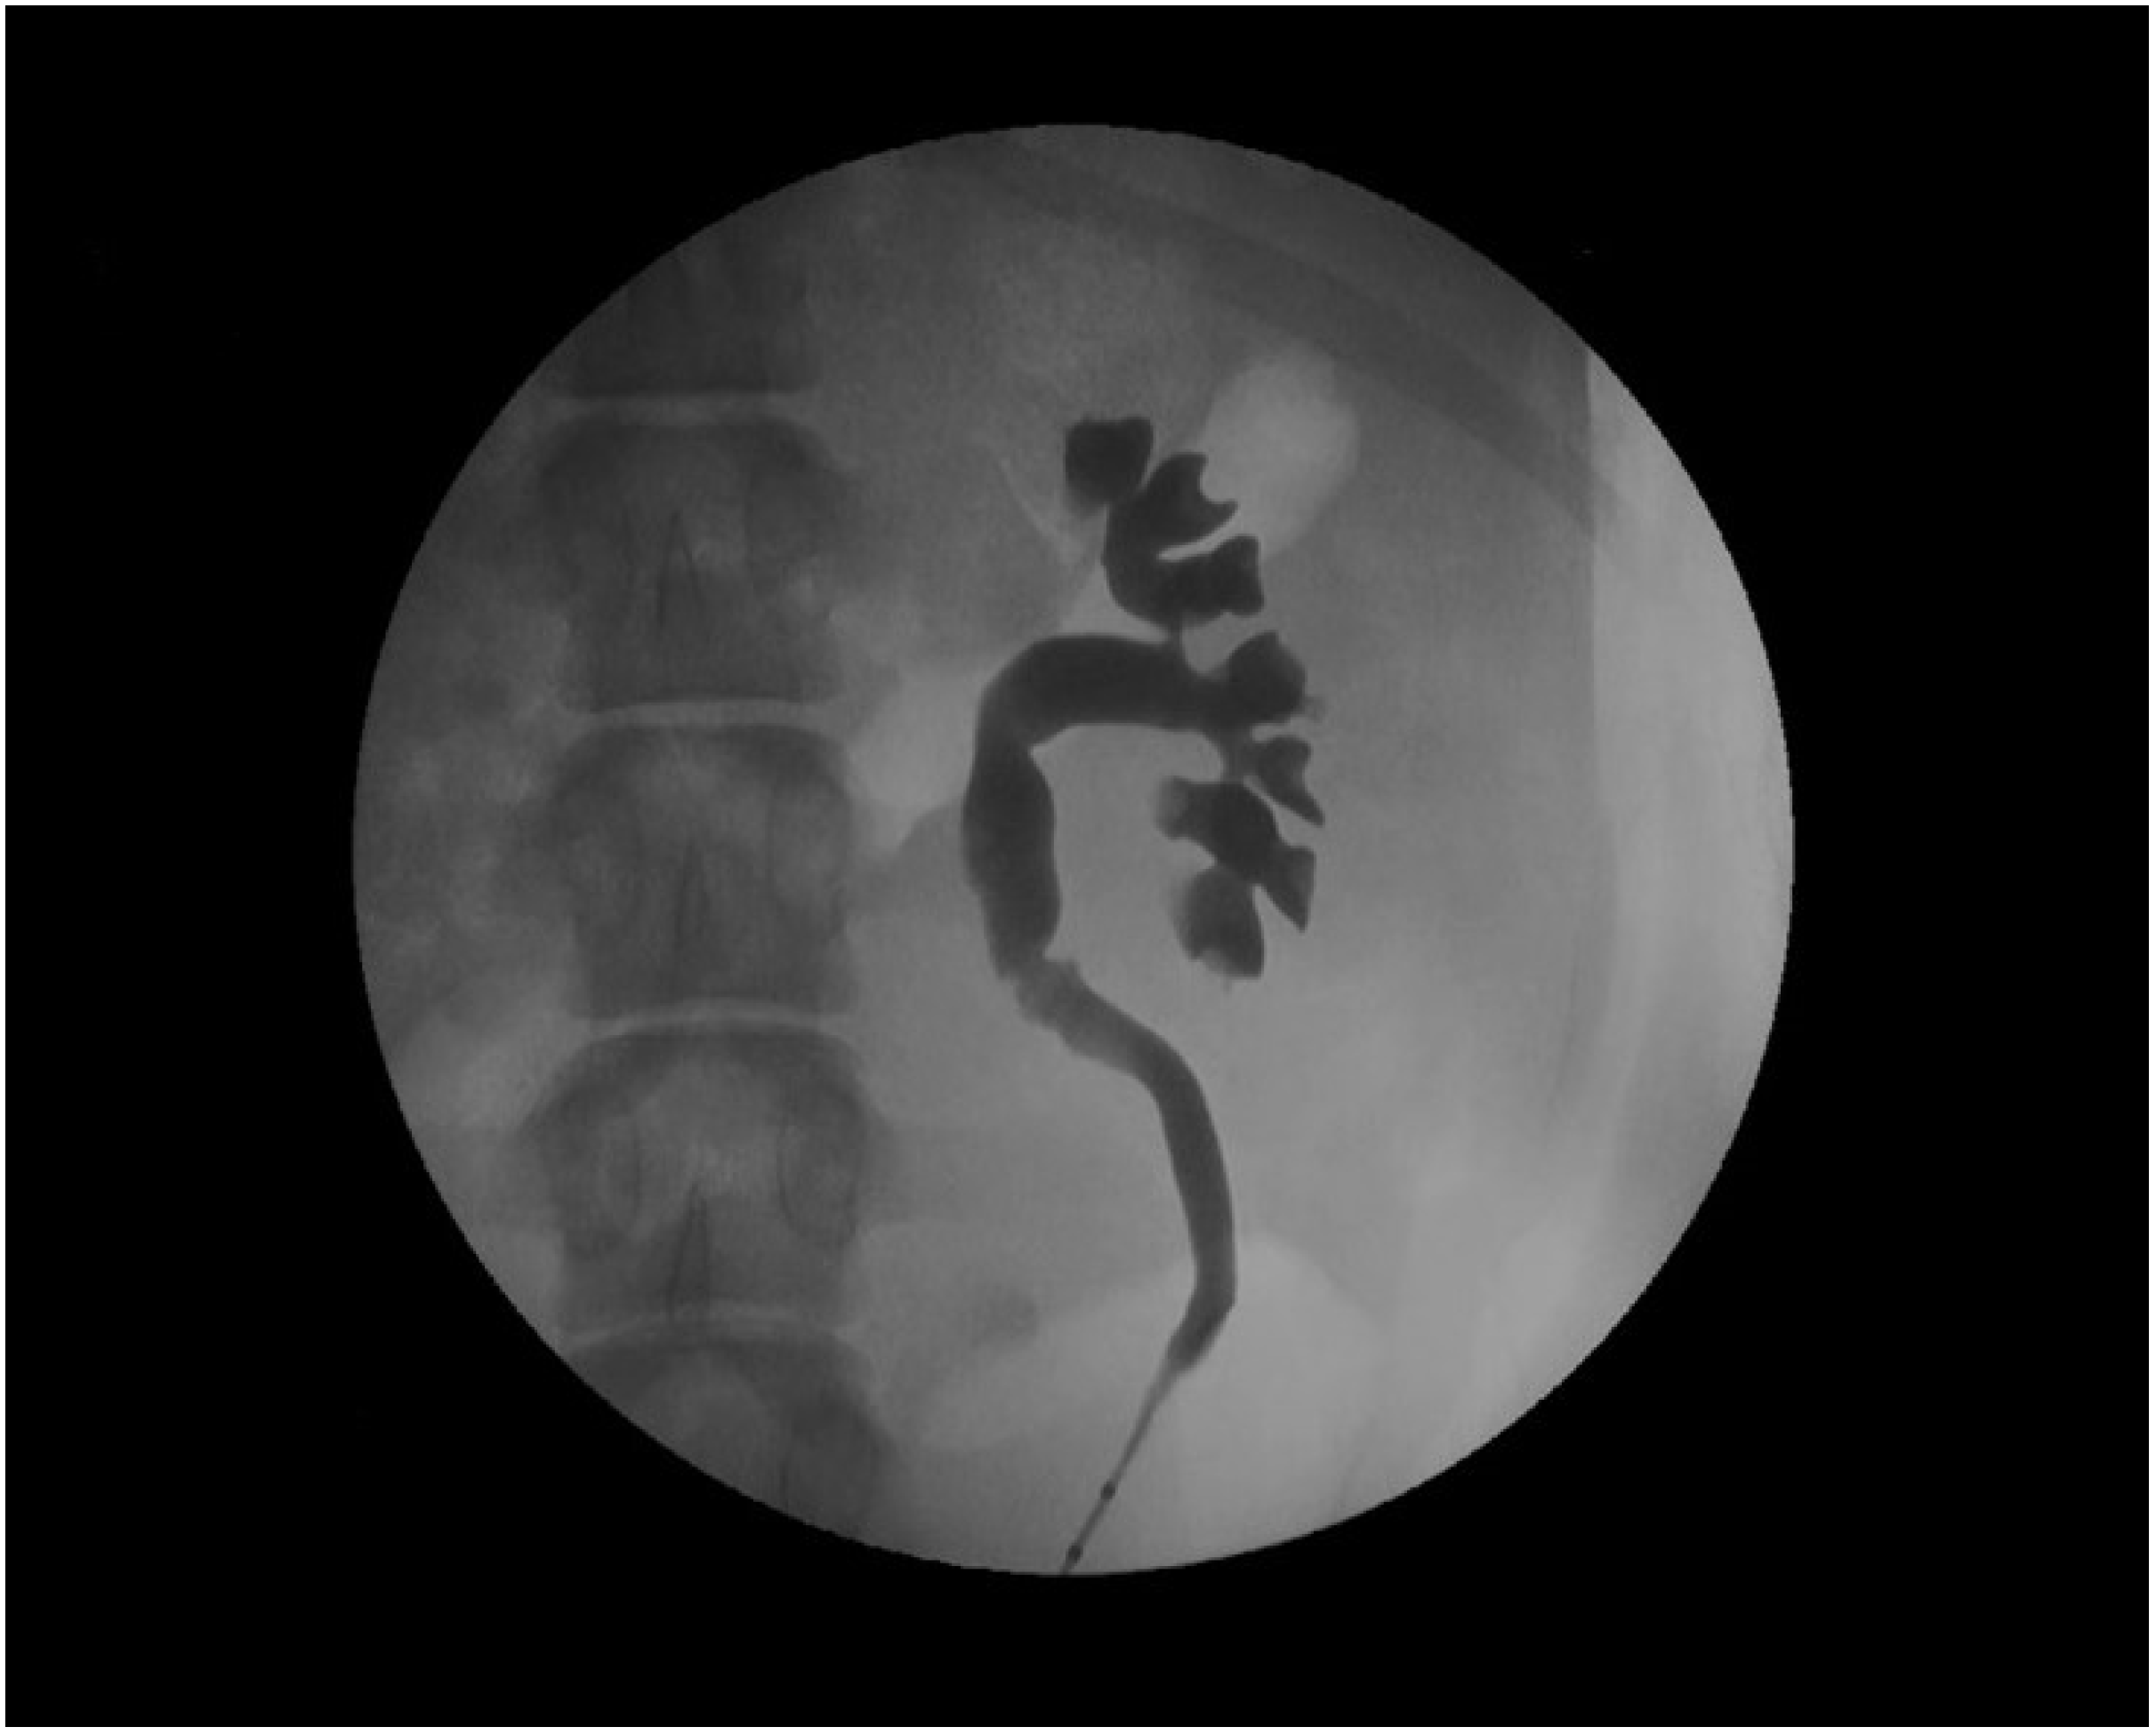

- Tunc, L.; Resorlu, B.; Unsal, A.; Oguz, U.; Diri, A.; Gozen, A.S.; Bedir, S.; Ozgok, Y. In vivo porcine model for practicing retrograde intrarenal surgery. Urol. Int. 2014, 92, 64–67. [Google Scholar] [CrossRef]

- Soria, F.; Rioja, L.A.; Blas, M.; Durán, E.; Usón, J. Evaluation of the duration of ureteral stenting following endopyelotomy: Animal study. Int. J. Urol. 2006, 13, 1333–1338. [Google Scholar] [CrossRef]

- Soria, F.; Morcillo, E.; Serrano, A.; Budía, A.; Fernandez, I.; Fernández-Aparicio, T.; Sanchez-Margallo, F.M. Evaluation of a new design of antireflux-biodegradable ureteral Stent in animal model. Urology 2018, 115, 59–64. [Google Scholar] [CrossRef] [PubMed]

- Soria, F.; Morcillo, E.; Pamplona, M.; Uson, J.; Sanchez-Margallo, F.M. Evaluation in an animal model of a hybrid covered metallic ureteral stent: A new design. Urology 2013, 81, 458–463. [Google Scholar] [CrossRef] [PubMed]